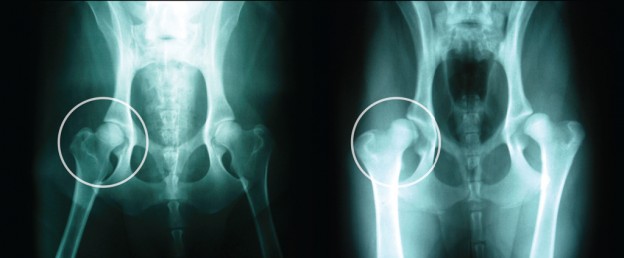

La displasia de cadera es una enfermedad ósea hereditaria que afecta a las articulaciones de la cadera de los perros. No es congénita, ya que las caderas son normales al nacer, sino que se desarrolla debido a un crecimiento desigual entre el sistema esquelético y los músculos.

Factores como el peso corporal, el tipo de ejercicio y las condiciones ambientales también pueden contribuir al desarrollo de la displasia de cadera. La frecuencia de displasia de cadera en el Pastor Blanco Suizo es del 19%. El diagnóstico de la displasia de cadera se basa en la información del propietario sobre el comportamiento del perro, así como en los signos clínicos y los datos radiográficos. Los síntomas clínicos pueden variar mucho de un individuo a otro e incluso pueden estar ausentes durante toda la vida del perro en muchos casos.

El diagnóstico radiográfico es especialmente valioso a partir de los 6 meses de edad. En cachorros de 3 a 4 meses, los síntomas pueden incluir dolor a la palpación de las caderas o al caminar. Si el dolor no es intenso, el cachorro puede mostrar sólo alteraciones de la marcha, debilidad en los cuartos traseros o tendencia a sentarse con frecuencia. El cachorro puede parecer torpe y tener músculos débiles en los cuartos traseros, con las patas traseras muy separadas y cruzadas. A medida que avanza la enfermedad, el cachorro puede experimentar dolor al caminar, lo que da lugar a una marcha característica de "conejito saltarín" y un movimiento excesivo de las caderas. En cachorros de 4 a 6 meses, el rápido crecimiento y el aumento de la actividad física pueden causar un dolor notable. El cachorro puede tumbarse y caer al suelo.

Radiográficamente, puede haber cambios en el borde acetabular y retraso en la conversión del fibrocartílago en cartílago hialino, junto con microfracturas y tensión en la cápsula articular y el ligamento redondo. En cachorros de 6 a 12 meses, la laxitud de la cápsula articular puede ser evidente tanto radiográficamente como mediante palpación. También puede haber dolor a la palpación y una marcha característica de "salto de conejo". En los perros adultos, la artrosis puede causar dolor tras el ejercicio prolongado o intenso, anomalías musculares durante el ejercicio, sinovitis, pasos cortos y disminución del movimiento de la cabeza femoral dentro del acetábulo. Estos perros pueden preferir sentarse a estar de pie y pueden presentar atrofia muscular en los muslos. La gravedad de la displasia de cadera puede clasificarse según la gradación de la FCI. El grado HDA indica que no hay signos de displasia, mientras que el grado HD E indica una displasia grave con anomalías y deformidades articulares marcadas. Existen tratamientos conservadores, terapéuticos y quirúrgicos para la displasia de cadera, pero ningún tratamiento puede restablecer totalmente la función normal de la articulación. El tratamiento conservador en perros jóvenes incluye limitar el ejercicio, controlar el aumento de peso y controlar el crecimiento rápido mediante el control de la dieta. Las opciones quirúrgicas incluyen la pectinectomía para aliviar el dolor y la triple osteotomía pélvica para corregir la inestabilidad articular. En conclusión, la displasia de cadera es una enfermedad ósea hereditaria que afecta a las articulaciones de la cadera de los perros. El diagnóstico se basa en los signos clínicos y los hallazgos radiográficos, y las opciones de tratamiento incluyen el tratamiento conservador y la cirugía. La gravedad de la displasia puede clasificarse según la gradación de la FCI.

La detección precoz y el tratamiento adecuado son cruciales para mejorar la calidad de vida de los perros con displasia de cadera.